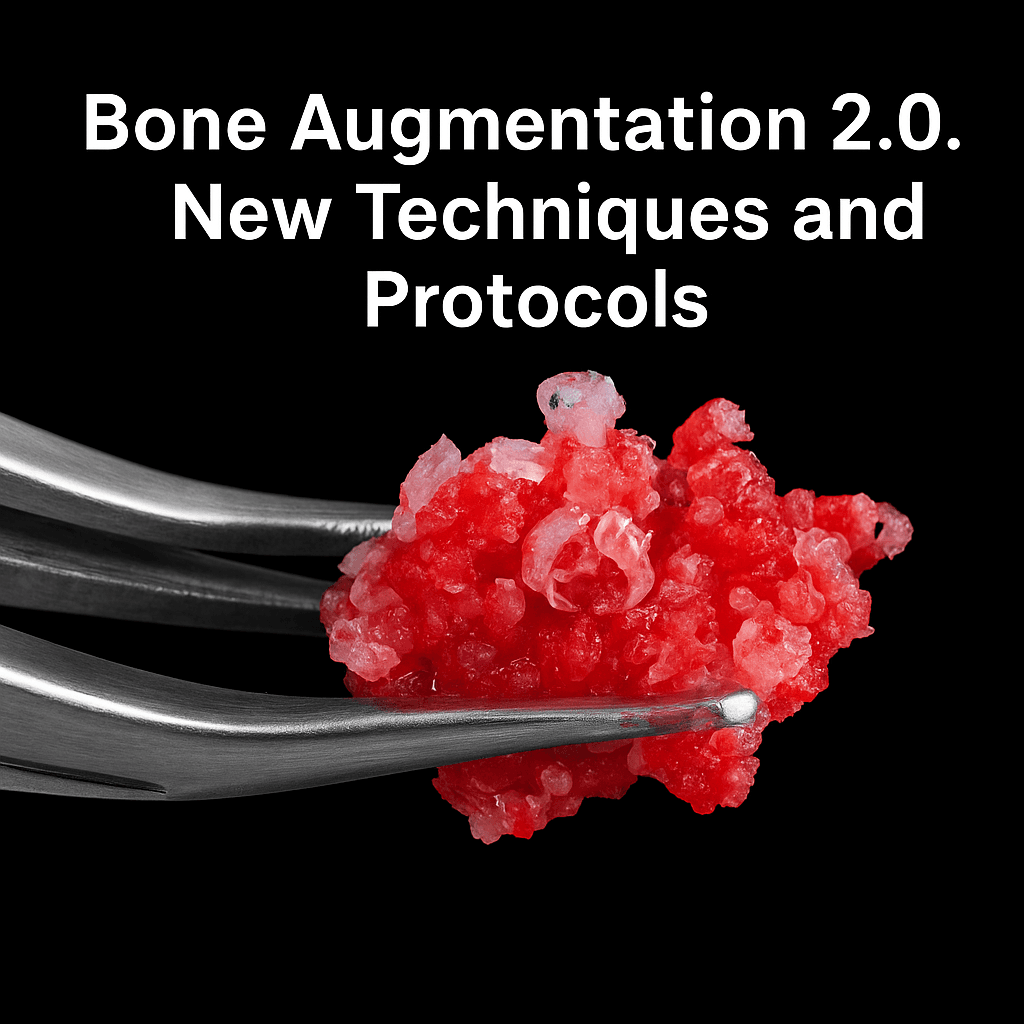

The course focuses on surgical techniques, autologous tissue and biomaterial management for vertical and/or horizontal bone augmentation, with the aim of successfully restoring edentulous ridges with implant-supported prostheses.

Bone-Augmentation Techniques

Bone-augmentation techniques – specifically proposed to increase bone volume in the posterior mandible – will be presented:

- Guided bone regeneration (GBR) by means of titanium mesh and onlay autologous block bone grafts (AOBG) for horizontal and vertical augmentation.

- How to approach and implement different surgical techniques, either used alone or in combination with autologous and/or heterologous graft materials to achieve alveolar bone augmentation (GBR and AOBG).